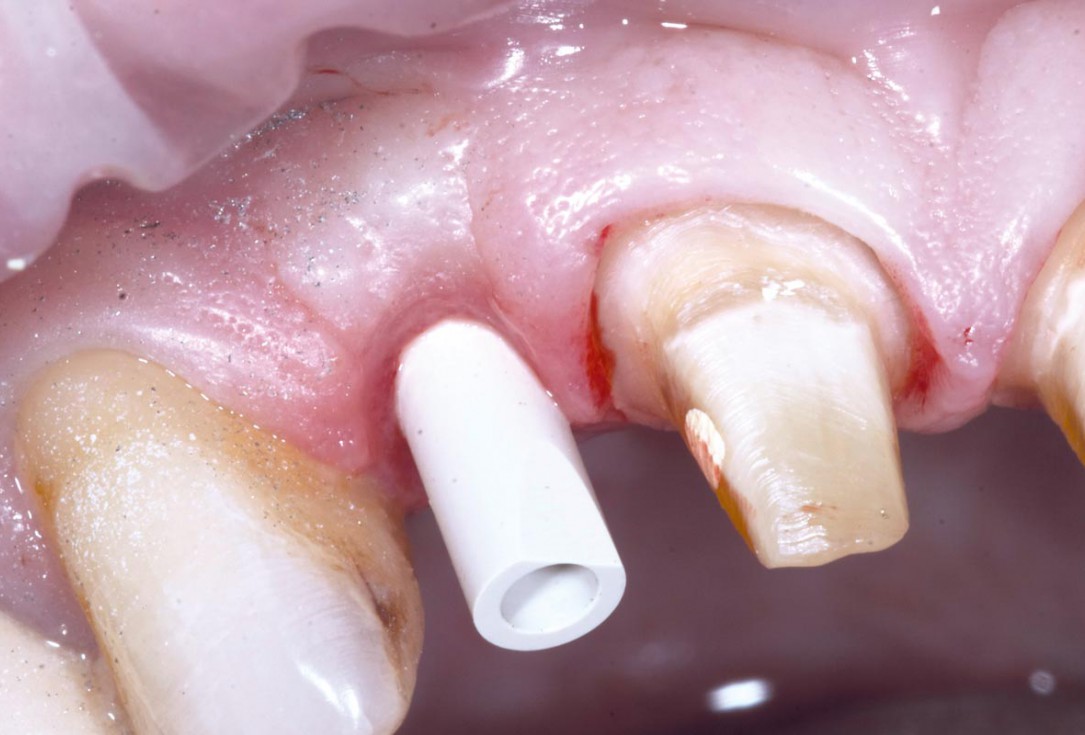

14/19 - Scanning the Implant fixture in situ with Digital Itero Scan including repreparation of adjacent teethBone augementation with maxresorb® - Dr. R. Cutts